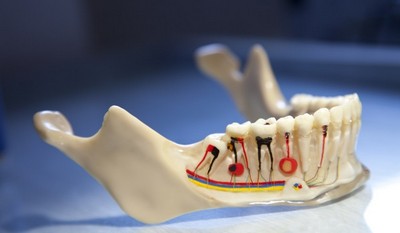

Периодонтит — воспалительное заболевание, в котором поражение происходит на верхушке корня зуба.

Его возникновение связано либо с отсутствием должного лечения пульпита, либо с некачественным пломбированием корневых каналов.

- Оценка результатов обследования, состоящего из осмотра ротовой полости, перкуссии, пальпации, зондирования входа в канал, температурных тестов, определения подвижности проблемного зуба, применения электроодонтодиагностики и радиовизиографии, проведения рентгенографии.

Важно! Данные, полученные при помощи рентгена, показывают полноценную картину заболевания. Насколько точно они будут расшифрованы — зависит от опытности врача.

Поражение корня

Патология поражает верхушку корня зуба. При более углублённом поражении следует глубокая очистка каналов, все остальные действия аналогичны принципам лечения недуга.